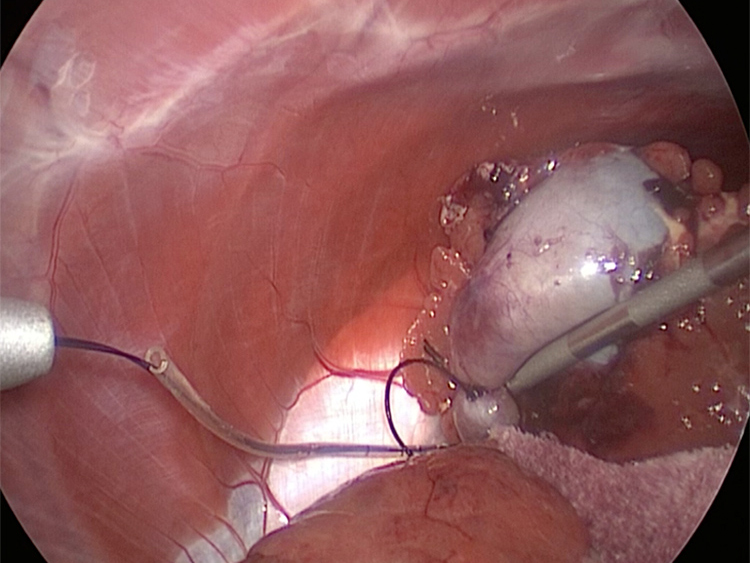

体の外に出すためお腹の中で袋に入れていきます。

このときに胆嚢と一緒にクリップやガーゼも回収します。そしてお腹の中をきれいにしていきます。

最後にお腹の中をきれいに洗浄していきます。

胆嚢の頸部に糸を通し動脈を確保しています。

胆嚢を少しずつ丁寧に肝臓から剥がしています。

回収袋にいれて体外に摘出していきます。

お腹の中を洗浄して終了となります。